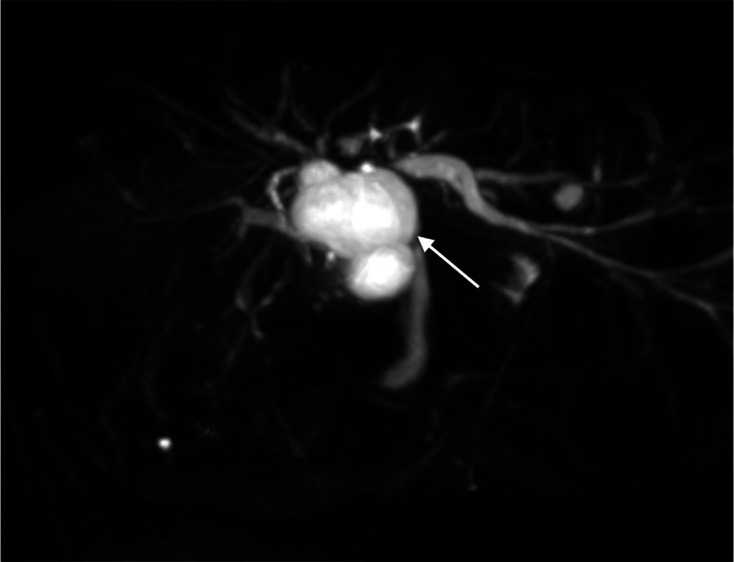

Methods: We report a case of cystic hepatic lesion near the confluence of bilateral intrahepatic ducts. MRCP shows direct anatomical communication between the lesion and the biliary tract, raising suspicion of a CC. Endoscopic ultrasound shows no communication between the lesion and biliary system. 99mTc-hepatic iminodiacetic acid scintigraphy (hepatobiliary scintigraphy) was subsequently performed, showing no tracer uptake in the concerned cystic hepatic lesion despite visualisation of gallbladder and transit of tracer into the intestine. Overall scintigraphic findings speak against a CC.